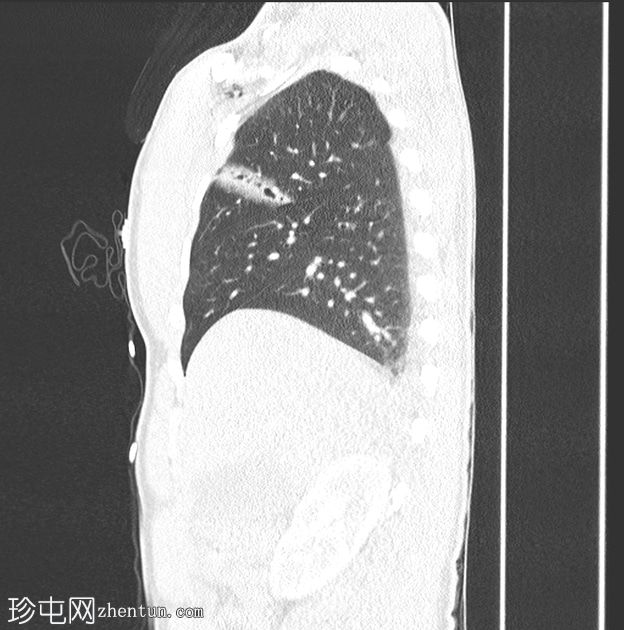

胸部

穿透伤

CT扫描

矢状面C+

动脉期

皮下气肿。右胸壁穿透伤,横穿右胸大肌,进入右前第三和第四肋骨之间的胸腔。右上叶49毫米裂伤,后方与水平裂隙相邻。伴有创伤性气囊和邻近毛玻璃影,与

肺

出血相符。右侧微小气胸。